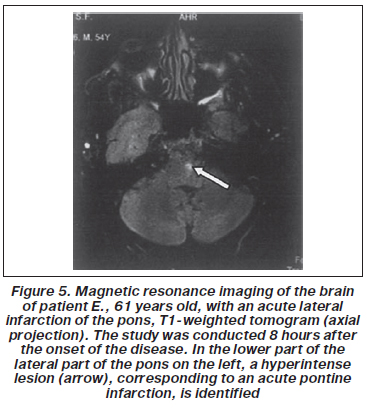

Patient E., 61 years old, was admitted to the department of cerebrovascular pathology. During a night of sleep, he suddenly developed systemic dizziness, repeated vomiting, impaired coordination, and weakness in the left limbs. In the morning, the patient developed deafness in the left ear and peripheral paralysis of the left facial muscles. Consciousness was not impaired.

Objectively: horizontal nystagmus, peripheral paresis of facial muscles on the left, deafness in the left ear. Hemihy-pesthesia of pain and temperature sensitivity on the right and cerebellar ataxia on the left. Tendon and periosteal reflexes from the upper limbs — S > D, from the lower limbs — D > S, positive bilateral Strümpel’s symptom. Muscle tone in the limbs is impaired.

Scales at admission: the NIHSS scale is 9 points, which indicates an average degree of stroke severity; according to the Hoffenberth scale — 22 points — for severe neurological impairment.

Ultrasound of the carotids, vertebral arteries, and transcranial dopplerography: hemodynamically marked locally atherosclerotic stenosis of the left carotid — 55 % and hemodynamically marked stenoses of both vertebral arteries (75–80 %). Brain MRI data are shown in Figure 5.

Diagnosis: incomplete lateral lower infarction of pons in a patient with hypertensive and atherosclerotic encephalopathy of the III degree.

A detailed clinical and radiological analysis showed that the center of the pontine infarction was localized in the lower lateral part, supplied with blood by the branches of the anterior infe-rior cerebella artery. Unilateral sudden hearing loss in the left ear was the result of occlusion of the internal auditory artery, which in 80 % of cases departs from the anterior inferior cerebella artery.